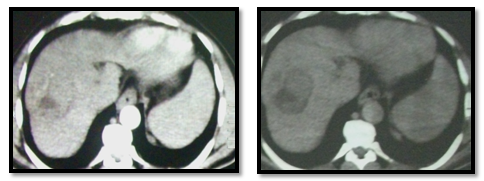

Case number (1), A 55years old female patient known to have hepatitis C virus with right hepatic lobe malignant lesion proved by imaging and elevated AFP. Her CT findings was right hepatic lobe (segment VI) well defined focal lesion of about 5cm showing early enhancement in arterial phase and rapid wash out in porto-venous and delayed phases, mild splenomegaly, no ascites. Her labs before doing any procedure was as follow (AFP 850, ALT 110, AST 90, Direct Bilirubin 1.1, Albumen 3 U/L and Creatinine 0.9). This patient was not candidate for surgery because she is cardiac patient with ejection fraction 38% and she were having poor bleeding profile with INR 1.5, that is medically controlled before starting the procedure.

CT images before doing any procedure: We decided to do RF as a starting treatment. She was complaining of mild post RF syndrome that controlled by medical treatment and after three weeks from RF ablation her AFP drop to 500 (Figure 2)

Figure 2 CT images before doing any procedure.